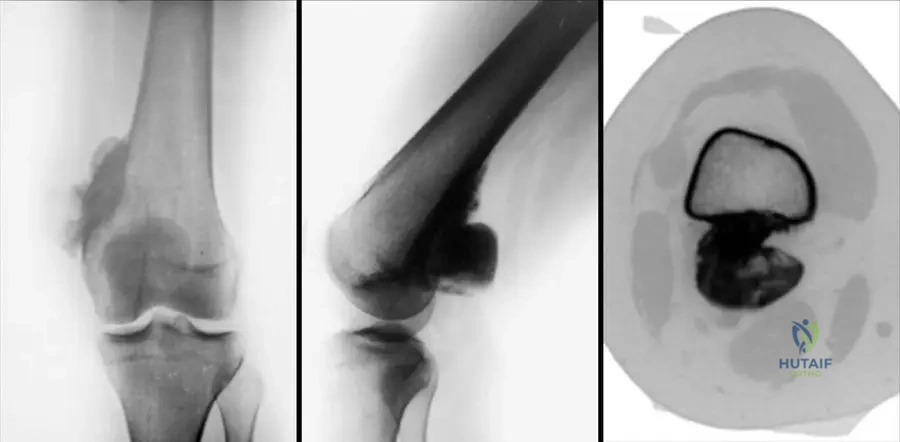

A 35-year-old male presents with a slowly growing mass on the posterior aspect of his distal femur. Radiographs reveal a heavily mineralized mass on the surface of the bone with a clear cleavage plane from the underlying cortex and no apparent medullary involvement. A CT scan confirms the absence of cortical or medullary continuity between the mass and the parent bone.

Rationale: Parosteal osteosarcoma typically presents as a heavily mineralized mass on the surface of the bone, most commonly on the posterior aspect of the distal femoral metaphysis, with no cortical or medullary continuity between the mass and the parent bone. This description perfectly matches the clinical vignette and radiographic findings. Conventional osteosarcoma is typically intramedullary and destructive. Periosteal osteosarcoma is a surface tumor but usually diaphyseal, partially mineralized, and may show malignant periosteal new bone formation. High-grade surface osteosarcoma is also on the surface but often shows more aggressive cortical involvement and incomplete mineralization. Chondrosarcoma would typically show chondroid matrix mineralization, not dense osteoid. The image (Fig. 8.69 a–c) clearly illustrates a parosteal osteosarcoma with its characteristic appearance.

Correct Answer: C